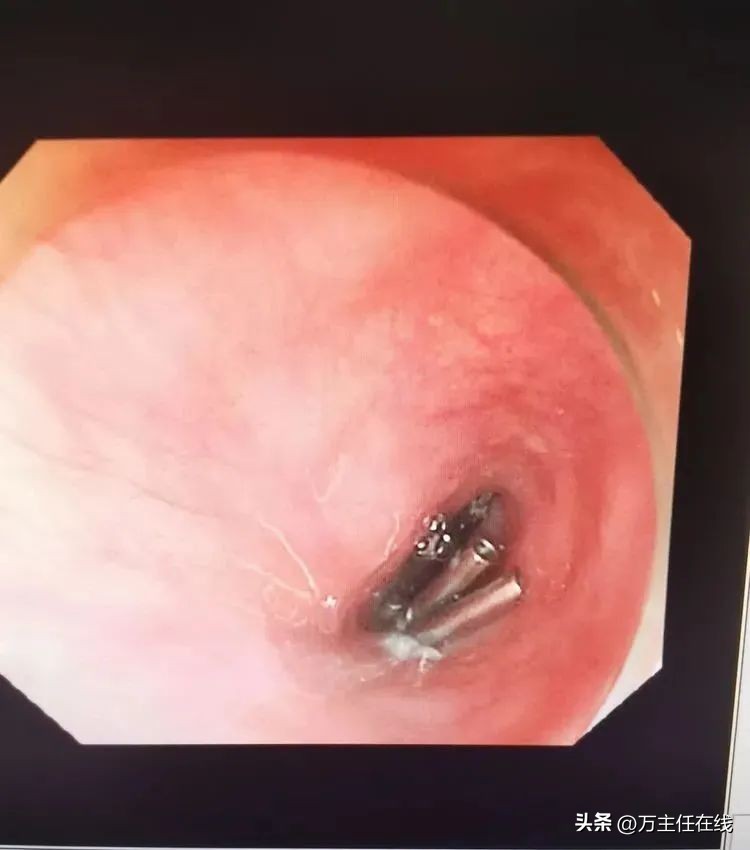

封闭食管粘膜下隧道上方之切口,恢复食管粘膜完整性